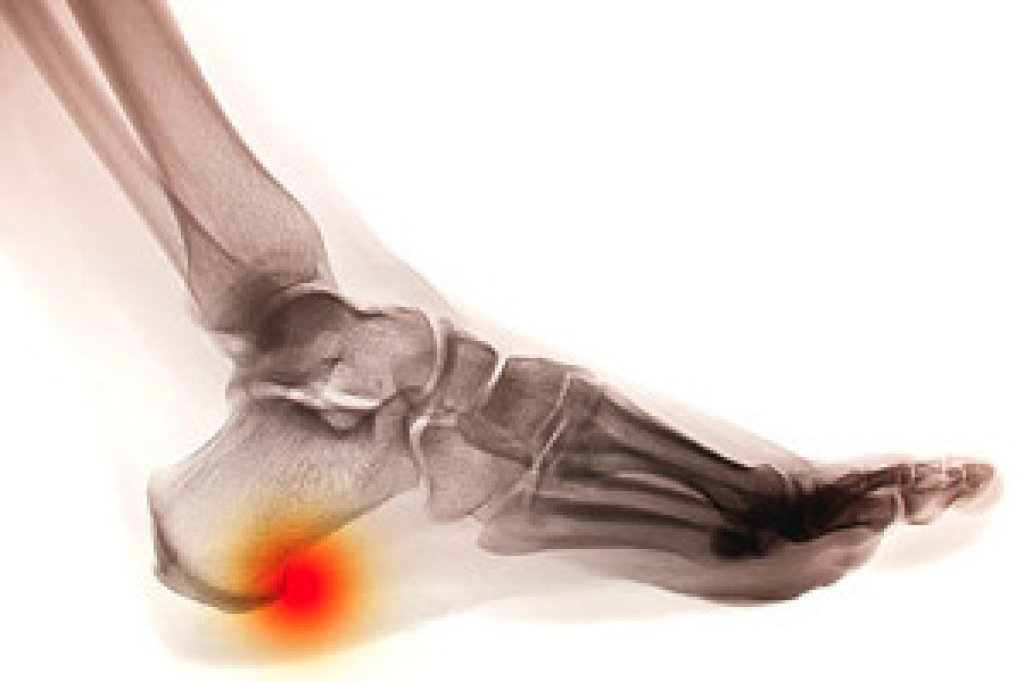

Morton’s neuroma is a foot condition that can develop in women who frequently wear high heels. This condition can result from having inadequate room for the toes to move freely in and can cause the nerve between the third and fourth toes to become compressed. Irritation and inflammation may accompany this, which can cause severe pain and discomfort. Patients who have Morton’s neuroma often say the sensation they feel is similar to having a pebble or marble in the shoe, in addition to numbness and tingling. Mild relief may also be found when soft insoles are worn, the feet are elevated, and shoes that are worn have a wide toe area. Existing medical conditions may contribute to Morton’s neuroma. These can include flat feet, bunions, and hammertoes. If you feel you may have this foot condition, it is advised that you speak to a podiatrist who can properly treat this ailment.

Morton's neuroma is a painful foot condition that commonly affects the areas between the second and third or third and fourth toe, although other areas of the foot are also susceptible. Morton’s neuroma is caused by an inflamed nerve in the foot that is being squeezed and aggravated by surrounding bones.

Morton’s neuroma is a very treatable condition. Orthotics and shoe inserts can often be used to alleviate the pain on the forefront of the feet. In more severe cases, corticosteroids can also be prescribed. In order to figure out the best treatment for your neuroma, it’s recommended to seek the care of a podiatrist who can diagnose your condition and provide different treatment options.